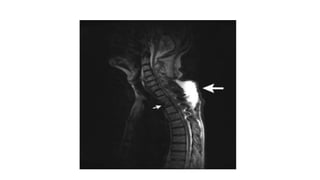

MRI

•Assessment of extradural abscesses / subligamentous spread.

MRI •Assessment of extraduralabscesses / subligamentous spread. •Skip lesions •Spinal cord involvement.